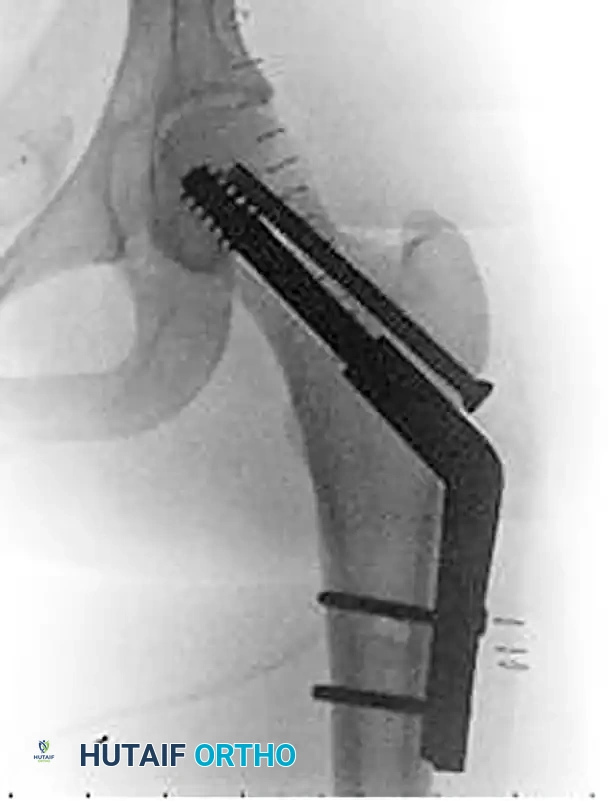

Figure 55-16B: Postoperative anteroposterior radiograph after operative reduction and fixation utilizing a fixed-angle sliding hip screw construct to provide controlled collapse while resisting excessive varus deformity.

- Fixed-Angle Devices: For vertically oriented fracture patterns (Pauwels Type III) or basicervical variants, a Sliding Hip Screw (SHS) or Dynamic Hip Screw (DHS) with a derotation screw provides superior biomechanical stability against shear forces compared to multiple cancellous screws.

Figure 55-16A: Preoperative radiograph at the time of injury demonstrating a displaced femoral neck fracture with significant biomechanical instability.